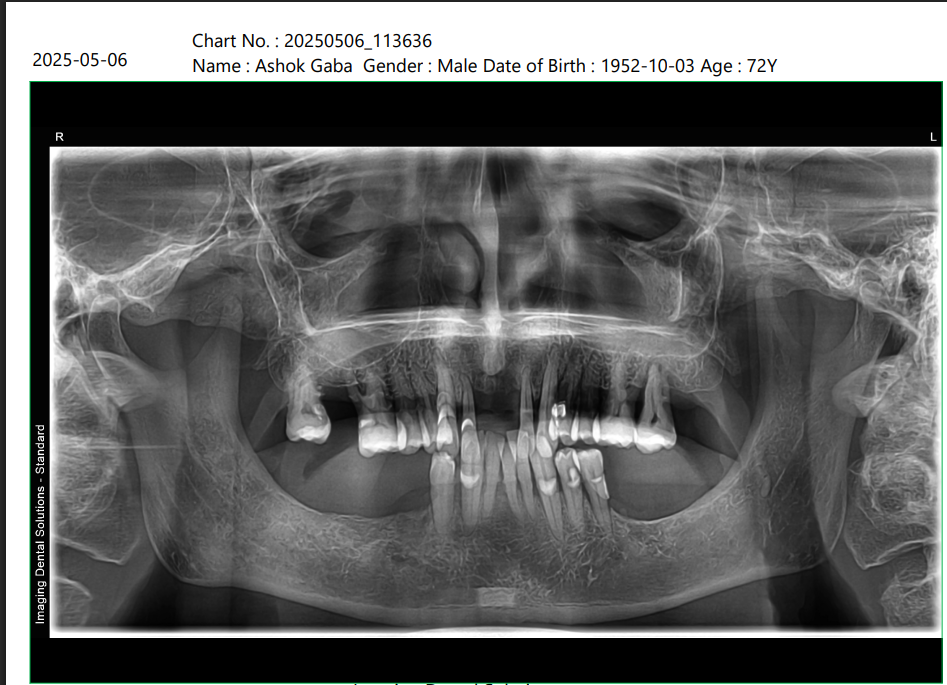

X-Ray Analysis

OPG — Before

Radiographic Findings

Multiple implants placed in both upper and lower jaw Implants are strategically angled and distributed Strong anchorage in available bone Proper full arch support for fixed teeth Balanced load distribution 👉 Clinical Meaning (simple explanation): We have created a strong foundation using implants, which act like artificial roots. These implants support fixed teeth, allowing the patient to chew normally again.